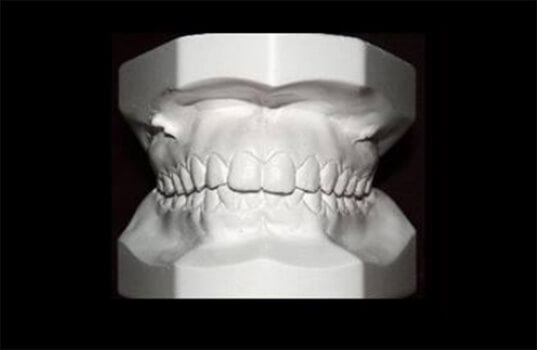

A prototipagem é um processo de fabricação de modelos de dentes ou outras estruturas da boca, geralmente em material plástico ou resina. É usada na odontologia como ferramenta para avaliar e planejar tratamentos, especialmente na ortodontia, prótese dentária e cirurgia bucal.

A prototipagem é realizada com base em imagens radiográficas, modelos de gesso da boca ou outros registros. O material plástico ou resina é moldado para representar a boca do paciente, com seus dentes e outras estruturas. O modelo permite que o dentista ou ortodontista veja o problema em questão e simule diferentes opções de tratamento, antes de realizar qualquer procedimento na boca do paciente.

A prototipagem também é útil para testar ajustes de próteses dentárias, como dentaduras, antes de fabricá-los definitivamente. Além disso, pode ser usada para ensinar pacientes sobre o tratamento que irão receber, ajudando-os a compreender o processo e os resultados esperados.